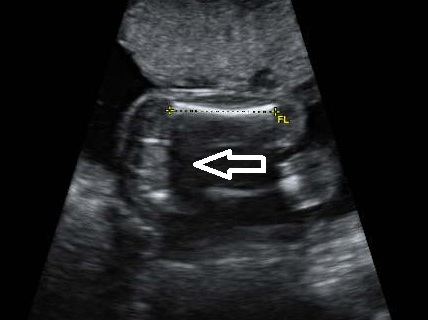

And this pic shows the tibia and fibula, not a tyical potty shot, but thought someone might see something???

Attachment 10655

Ive put the arrows in